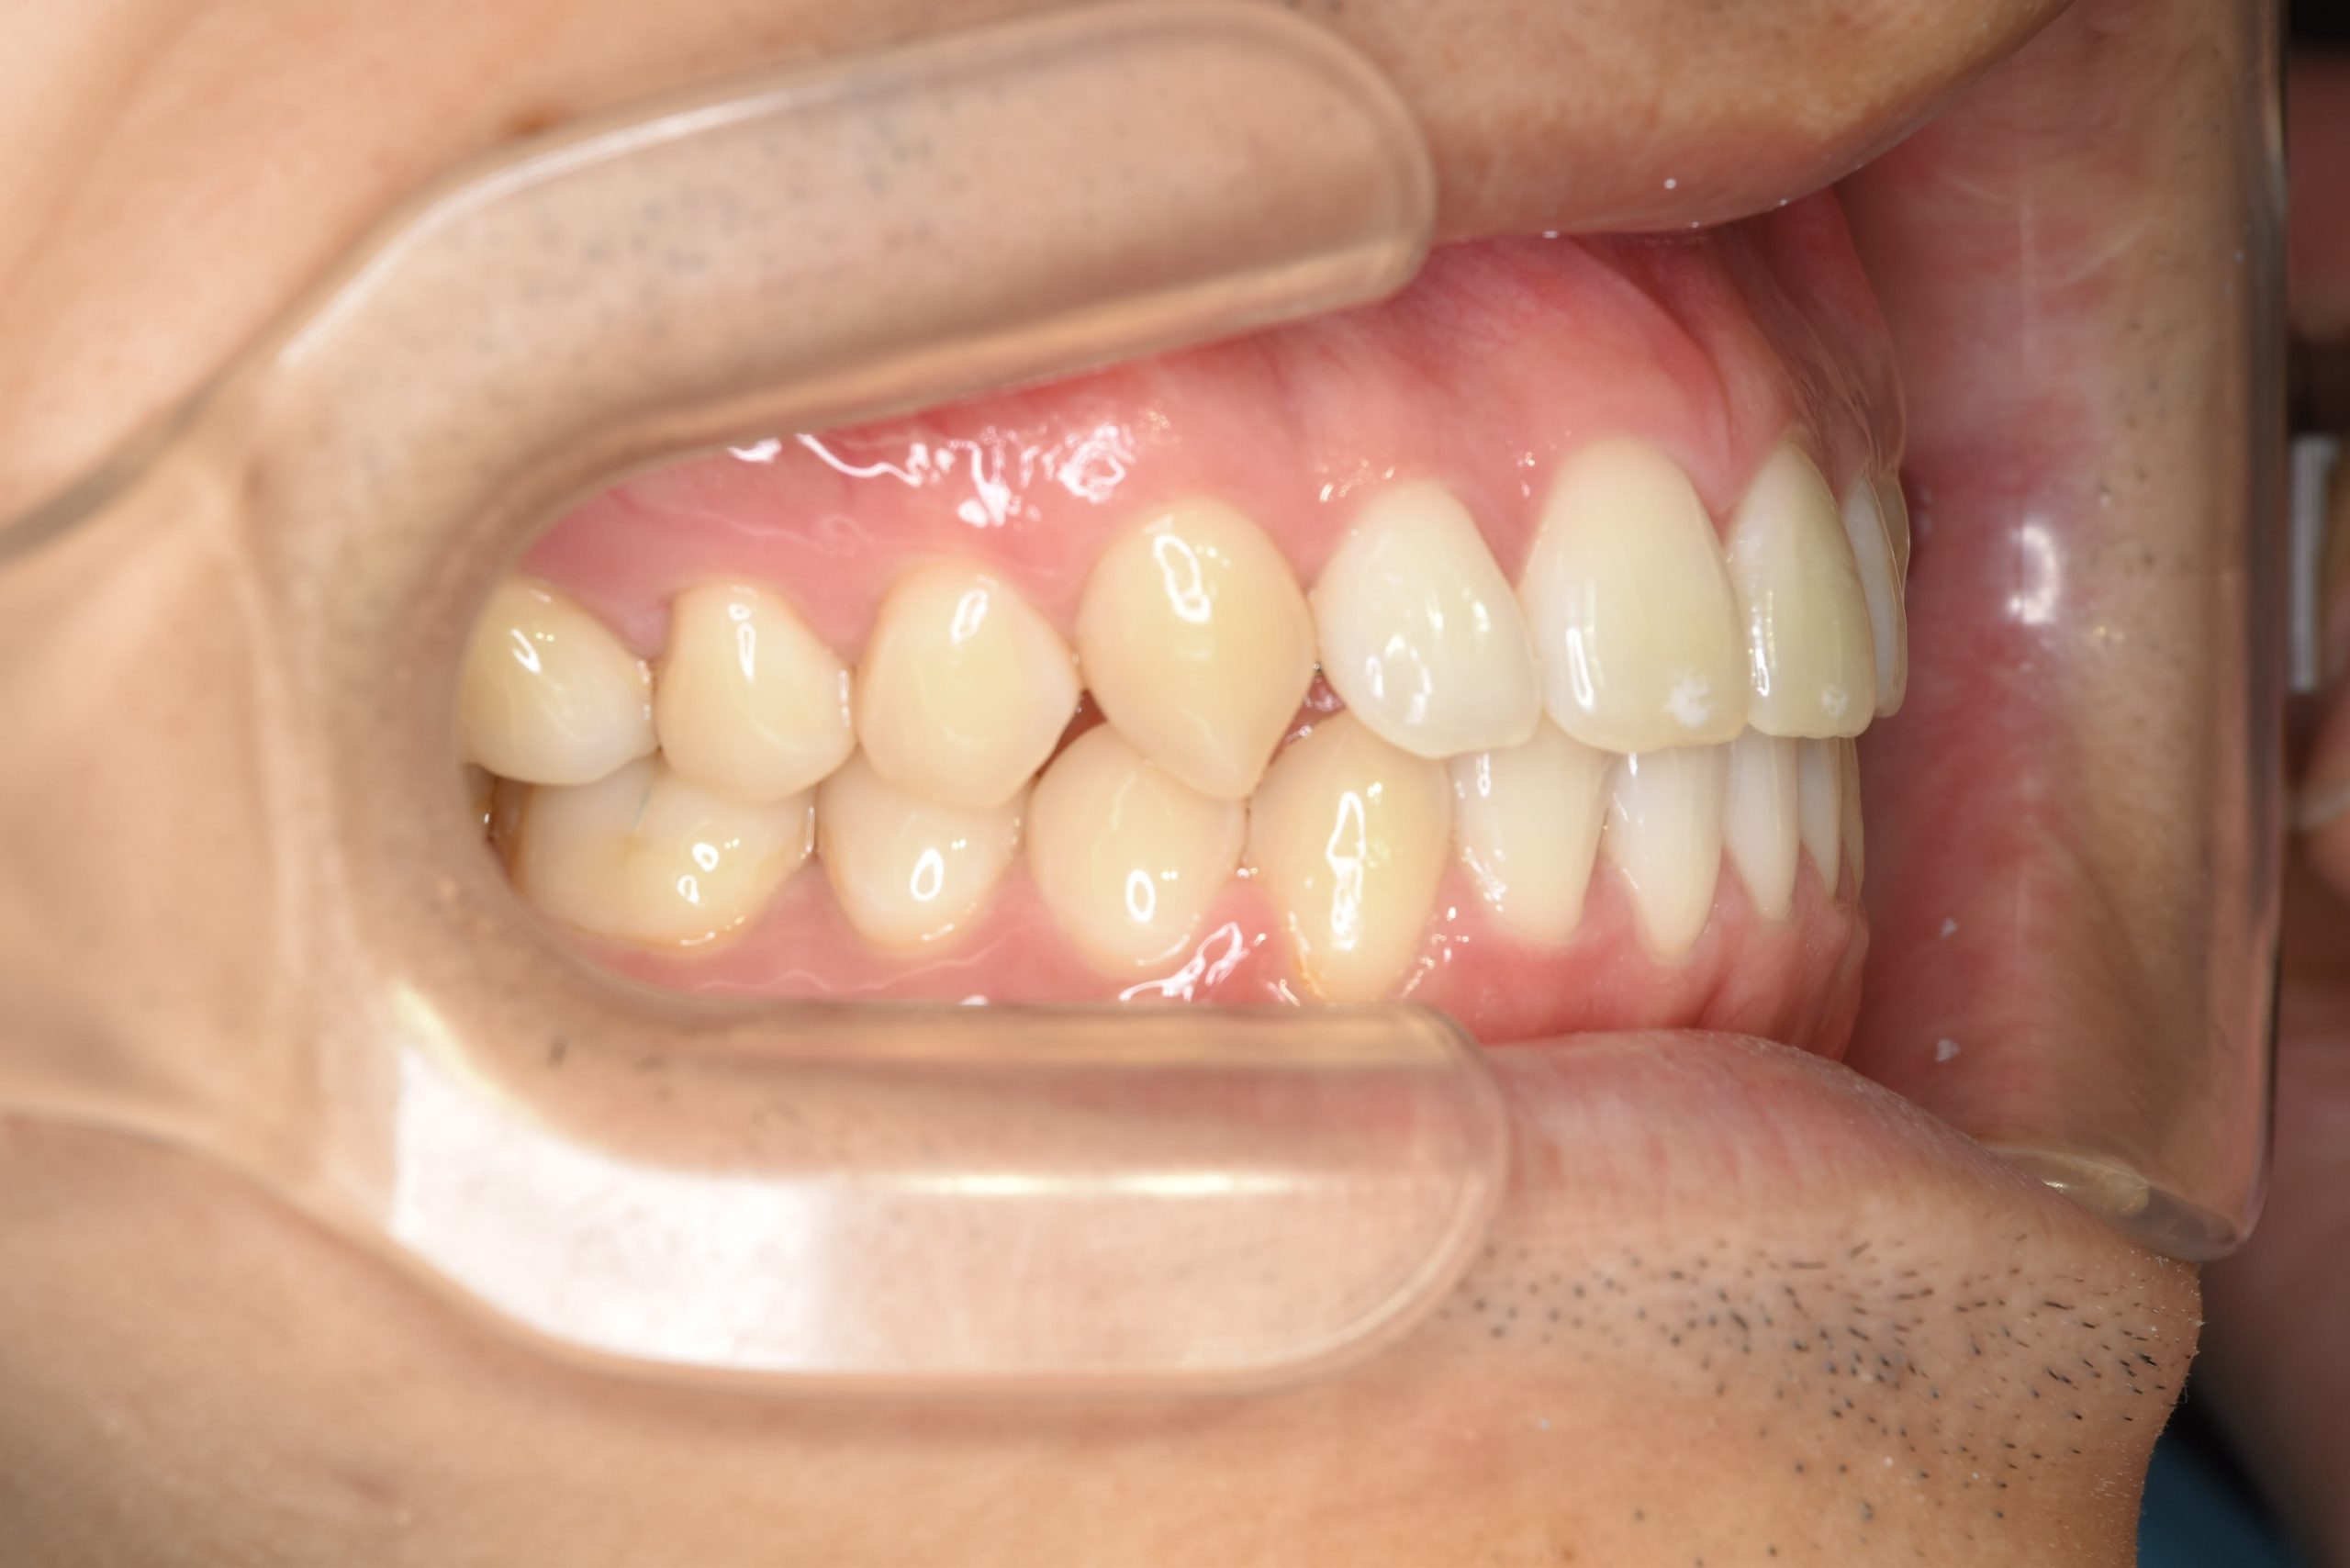

ビフォー

ワイヤー矯正治療|症例_495

主訴 受け口|かみ合わせ|面長

施術内容 MSEと下顎リンガルアーチを用いて上下顎骨を拡大した。

その後マルチブラケット装置とミニインプラントを用いて

非抜歯で歯牙を配列し、良好な咬合を獲得した。

下口唇の突出感と鼻閉症状は改善した。

治癒期間 2年1か月間